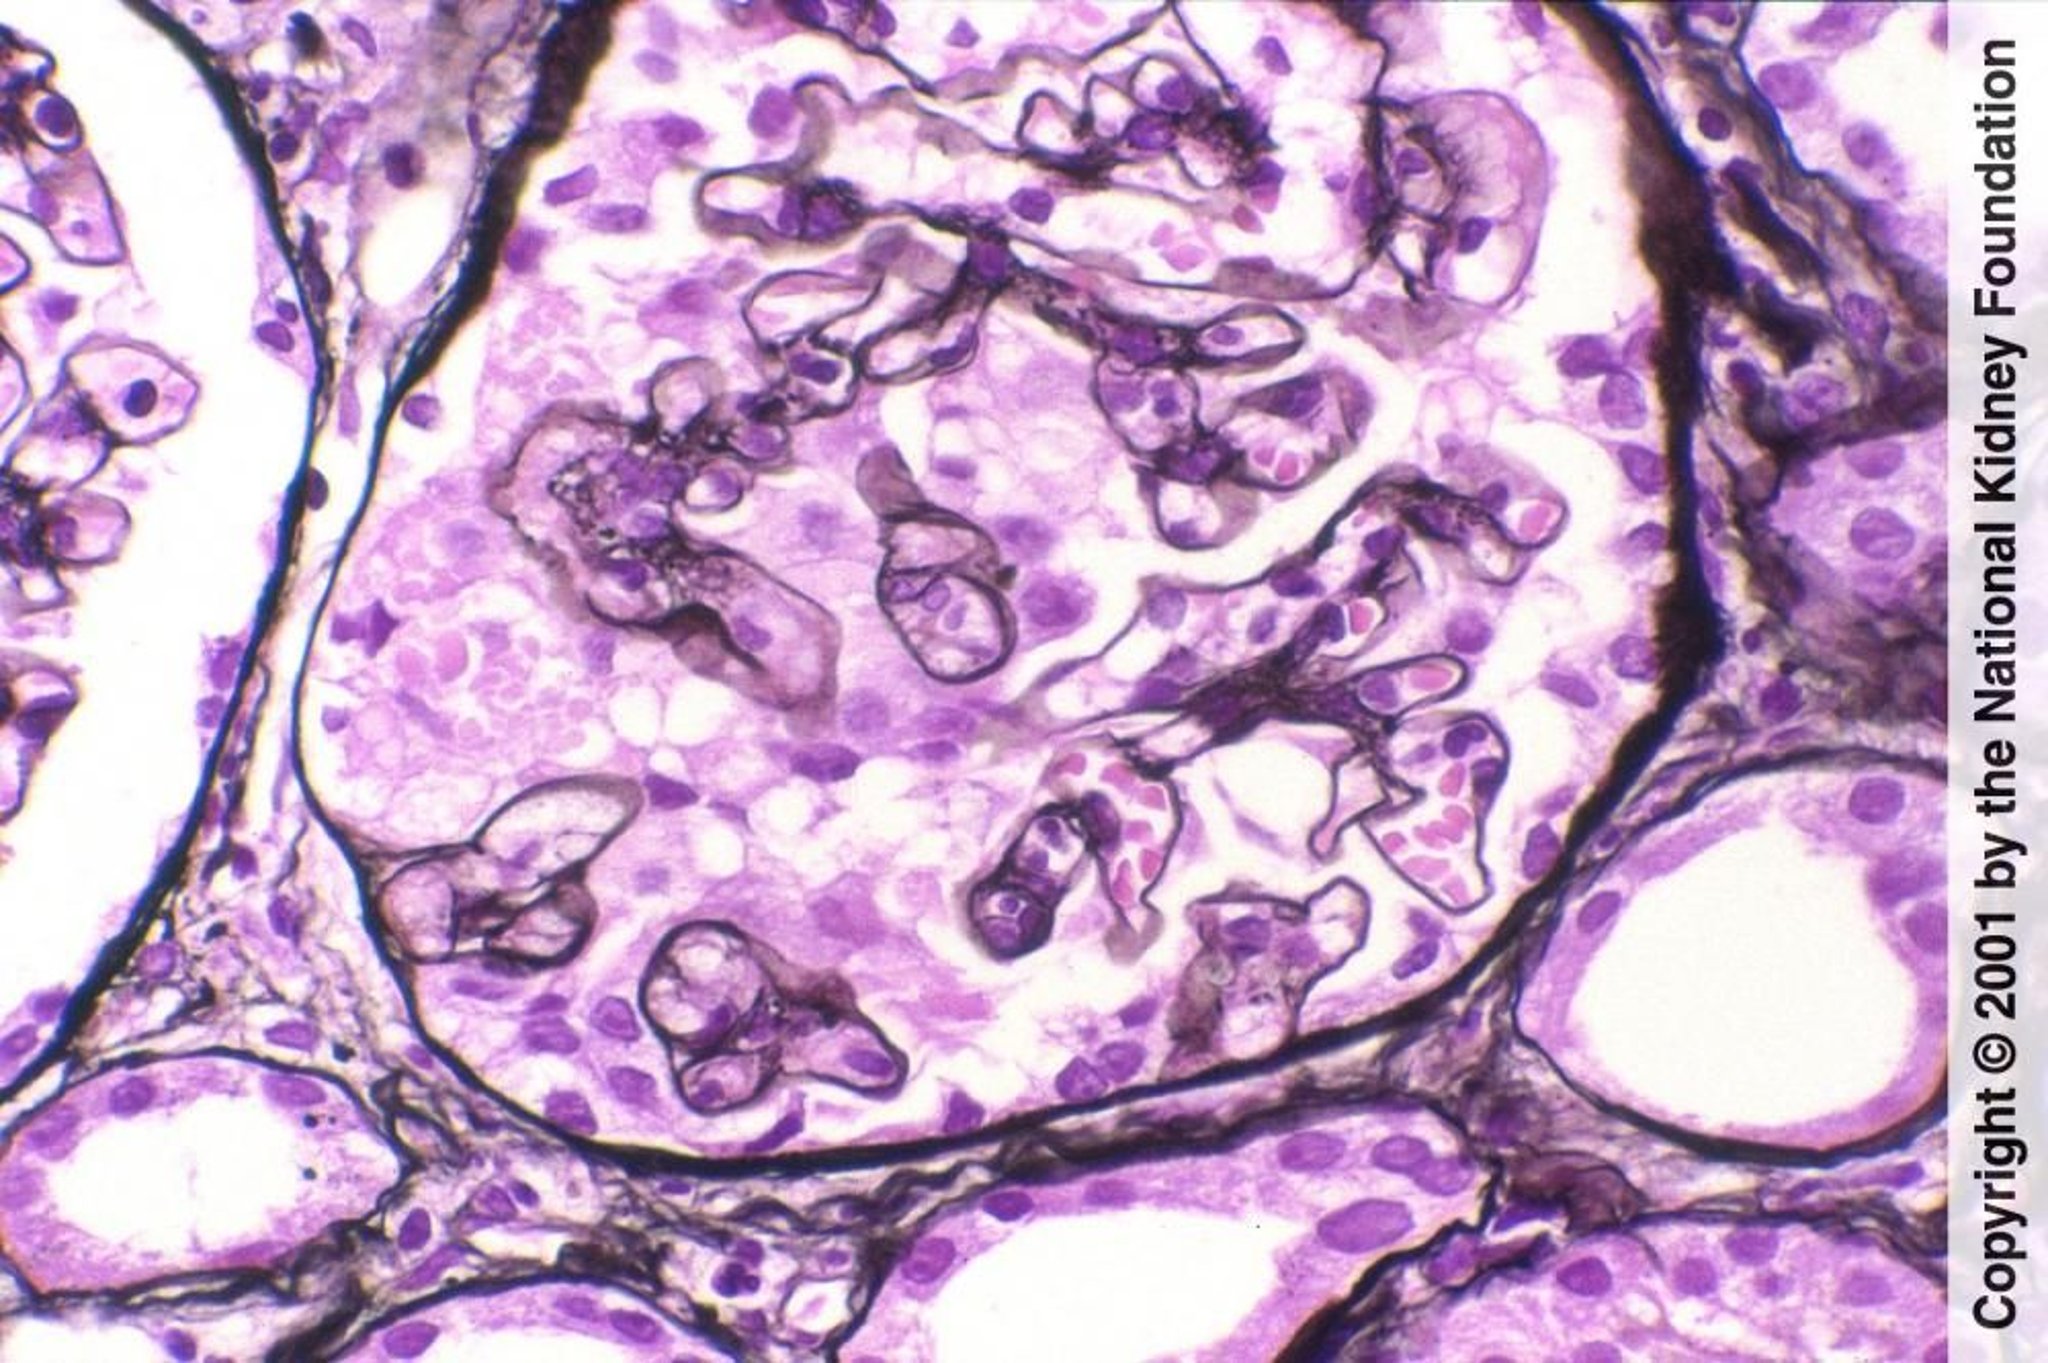

上の画像は糸球体の右側を示している。糸球体は分節性に硬化しており,内腔が消失した毛細血管および増加したメサンギウム基質で構成されている。残りの糸球体は正常である(PAM染色,400倍)。下の画像では,滑らかな硝子様物質と定義されるヒアリンが,血漿タンパク質の壁内滲出(壁外への滲出の逆)によりもたらされている。これは高頻度に発生し,診断に有用ではない(PAM染色,400倍)。

上の画像は糸球体の右側を示している。糸球体は分節性に硬化しており,内腔が消失した毛細血管および増加したメサンギウム基質で構成されている。残りの糸球体は正常である(PAM染色,400倍)。下の画像では,滑らかな硝子様物質と定義されるヒアリン